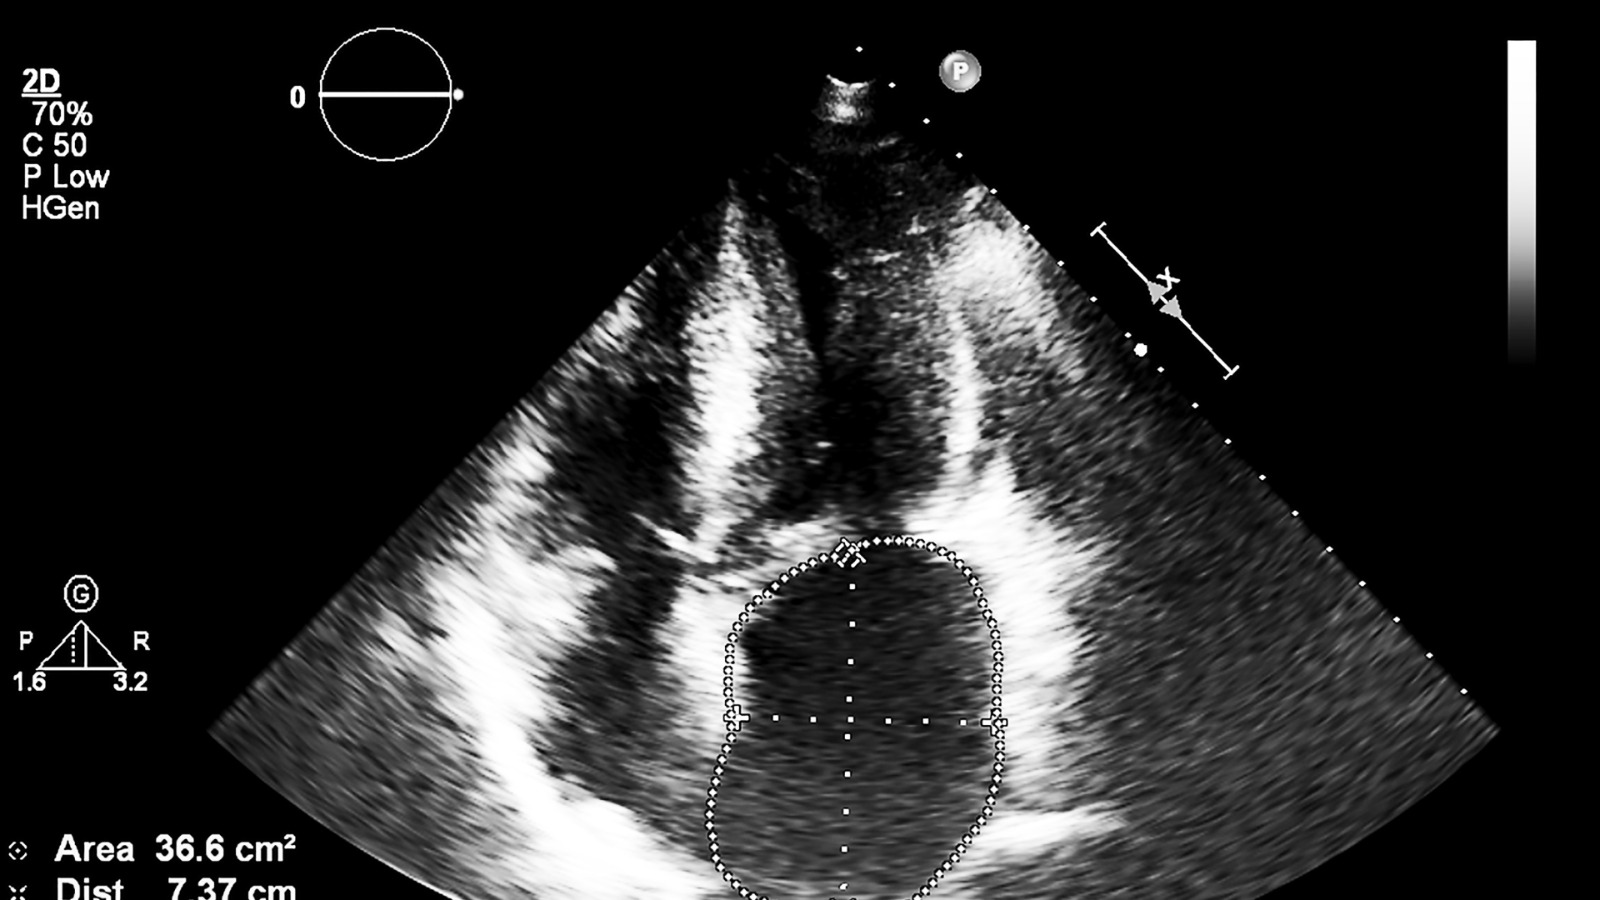

Echocardiography with Expertise in 3D & 4D Echocardiography

Expertise in Speckle Tracking Echocardiography- Strain Imaging Echocardiography

Transesophageal Echocardiography